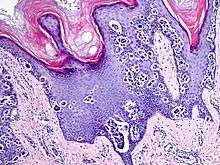

An acral nevus (also known as a "Melanocytic nevus of acral skin",[1] and "Melanocytic nevus with intraepidermal ascent of cells"[1] (MANIACS)) is a cutaneous condition characterized by a skin lesion that is usually macular or only slightly elevated, and may display uniform brown or dark brown color, but often with linear striations.[1]:1726